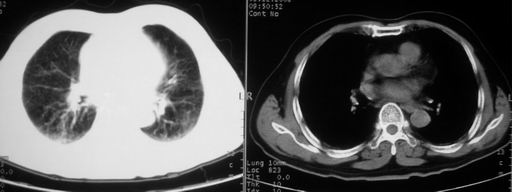

男,78岁,咳嗽、咳痰、发热入院,抗炎治疗一周后已退热,咳血似痰。

10月3日片: